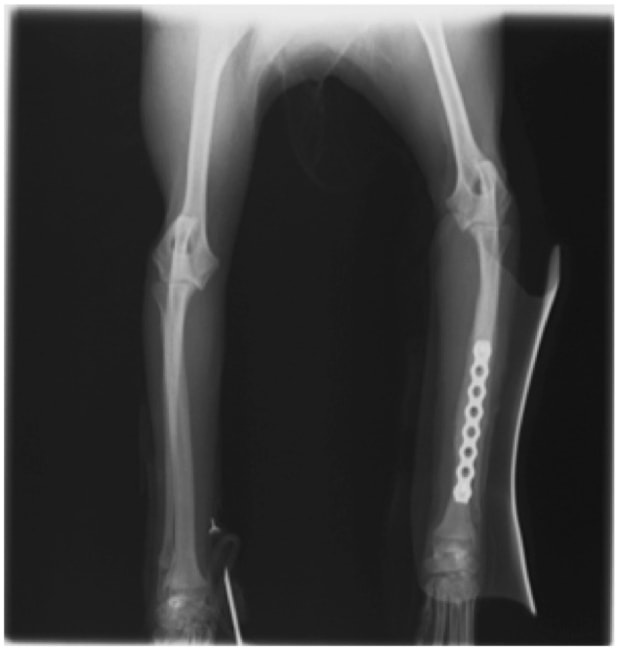

トイプードル 右遠位橈尺骨短斜骨折のALPSによる内固定

当院ではAdvanced Locking plate system(ALPS)と、Locking compression plate system(LCPS)という骨接合法で骨折症例の治療を行っています。

従来型のプレートのように広い面積で骨と接するプレートを用いて固定を行った場合、プレート下の骨はプレートとの接触面において血行が絶たれ壊死し、それがリモデリングされると骨密度が低下する。この骨密度の低下防ぐために、骨折部局所への血行を温存することの重要性が近年改めて認識されるようになってきている。Advaed Locking Plate System (ALPS)は従来型のプレートシステムの欠点を改良し、より使いやすく、より骨への血行を阻害しないようにというコンセプトで作られた。

LCPは、スクリュー(ネジ)とプレート(金属の板)をロックする特殊な構造により骨折部位を固定する新しい世代のプレートシステムです。ひとつのホールでロッキングスクリューとスタンダードスクリューの使用を選択できるユニークな構造をしているため、骨折断端間の圧迫を目的とした従来型プレート固定法に加え、高い角度安定性を有するロッキングスクリューを用いた固定法の選択が可能です。従来のプレートシステムでは困難だった部分の骨折や癒合不全の症例に高い治療効果をもたらします。